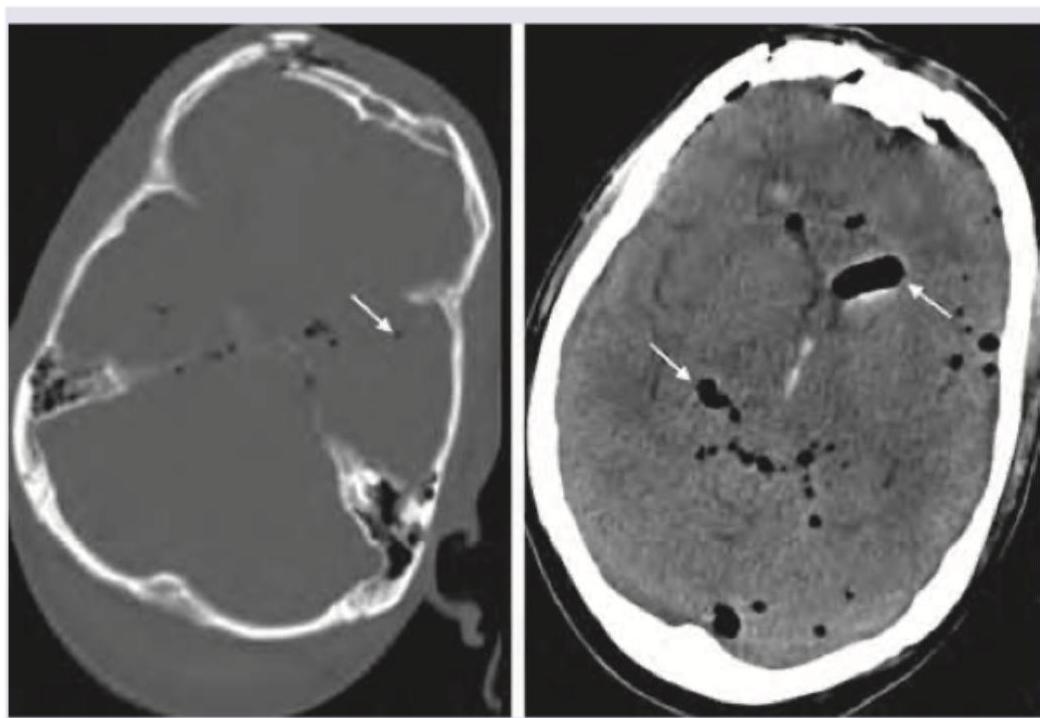

A 60-year-old male presents to the emergency department on the second day of symptom onset with progressive deterioration of consciousness due to large right MCA territory infarct. Which of the following is the most appropriate management? (Image: img-179.jpeg)

Explanation: ***Decompressive surgery*** - A large **MCA territory infarct** causes significant brain edema, leading to increased **intracranial pressure** and progressive deterioration of consciousness, especially on day 2. - **Decompressive craniectomy** is often necessary in such cases to reduce pressure, prevent herniation, and improve outcomes by removing a portion of the skull. *Anticoagulation* - Anticoagulation is primarily used for preventing future thrombotic events due to conditions like **atrial fibrillation**, or for managing an evolving stroke if there's no major hemorrhage risk. - In the setting of a **large ischemic stroke** with significant edema and risk of hemorrhagic transformation, anticoagulation can increase the risk of bleeding into the infarct. *Dual antiplatelet therapy* - **Dual antiplatelet therapy** (DAPT) is typically used to prevent recurrent ischemic events following a **minor stroke** or **transient ischemic attack (TIA)**. - It is not indicated for managing acutely deteriorating consciousness due to brain edema in a **large established infarct**. *Mechanical thrombectomy* - **Mechanical thrombectomy** is an acute intervention performed within a narrow time window (typically up to 24 hours in select patients, but ideally much earlier) to remove the clot and **restore blood flow**. - On the second day of symptom onset, with a fully developed **large infarct** and progressive neurological deterioration due to edema, the brain tissue is likely already irreversibly damaged, making thrombectomy ineffective and potentially harmful due to reperfusion injury.